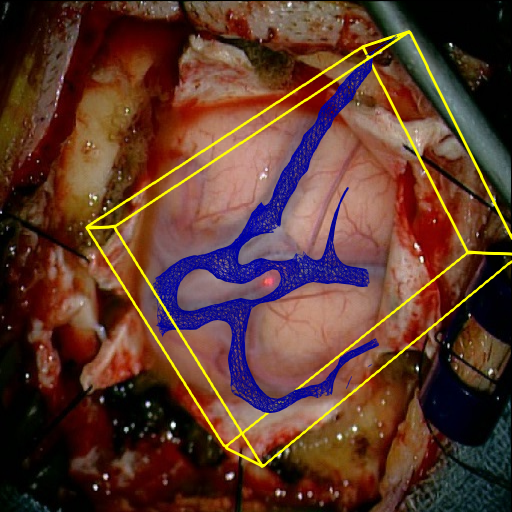

We tested our method retrospectively on 6 clinical datasets from 6 patients (cases) (see Fig. 5). These consisted of preoperative T1 contrast MRI scans and intraoperative images of the brain surface after dura opening. Cortical vessels around the tumors were segmented and triangulated to generate 3D meshes using 3D Slicer. We generated 100 poses for each 3D mesh (i.e.: each case) and used a total of 15 unique textures from human brain surfaces (different from our 6 clinical datasets) for synthesis using . In order to account for potential intraoperative brain deformations [4] we augment the textured projection with elastic deformation [21] resulting in approximately 1500 images per case. The surgical images of the brain (left image of the stereoscopic camera) were acquired with a Carl Zeiss surgical microscope. The ground-truth poses were obtained by manually aligning the 3D meshes on their corresponding images.

Test and Comparison on Clinical Images

We compared our method (Ours) with segmentation-based methods (ProbSEG) and (BinSEG) [7]. These methods use learning-based models to extract binary images and probability maps of cortical vessels to drive the registration. We report in Tab. 1 the distances between the ground truth and estimated poses. Our method outperformed ProbSEG and BinSEG with an average ADD error of mm compared to mm and mm, respectively. Our errors remain below clinically measured neuronavigation errors reported in [4], in which a mm average initial registration error was measured in 15 craniotomy cases using intraoperative ultrasound. Our method outperformed ProbSEG in 5 cases out of 6 and BinSEG in all cases and remained within the clinically measured errors without the need to segment cortical vessels or select landmarks from the intraoperative image. Our method also showed fast intraoperative computation times. It required an average of only milliseconds to predict the pose (tested on research code on a laptop with NVidia GeForce GTX 1070 8GB without any specific optimization), suggesting a potential use for real-time temporal tracking.

Fig. 5 shows our results as Augmented Reality views with bounding boxes and overlaid meshes. Our method produced visually consistent alignments for all 6 clinical cases without the need for initial registration. Because our current method does not account for brain-shift deformation, our method produced some misalignment errors. However, in all cases, our predictions are similar to the ground truth.